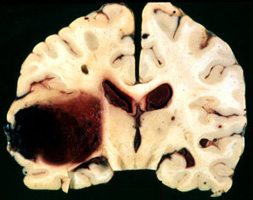

Question 24: A 72 year old woman with a one year history of declining memory developed sudden headache

and decreased consciousness and collapsed while washing dishes. Neuropathological examination revealed the lesion below.

What is the most likely cause of the lesion?

Incorrect! The lesion is a lobar hemorrhage. The cause, in this case, was cerebral amyloid angiopathy.

Patients with CAA may have Alzheimer disease.

Hypertension can cause similar lesions. Anticoagulation can cause a variety of hemorrhages,

usually associated with head trauma.rebral arteries.

Correct. The lesion is a lobar hemorrhage. The cause, in this case, was cerebral amyloid angiopathy.

usually associated with head trauma.